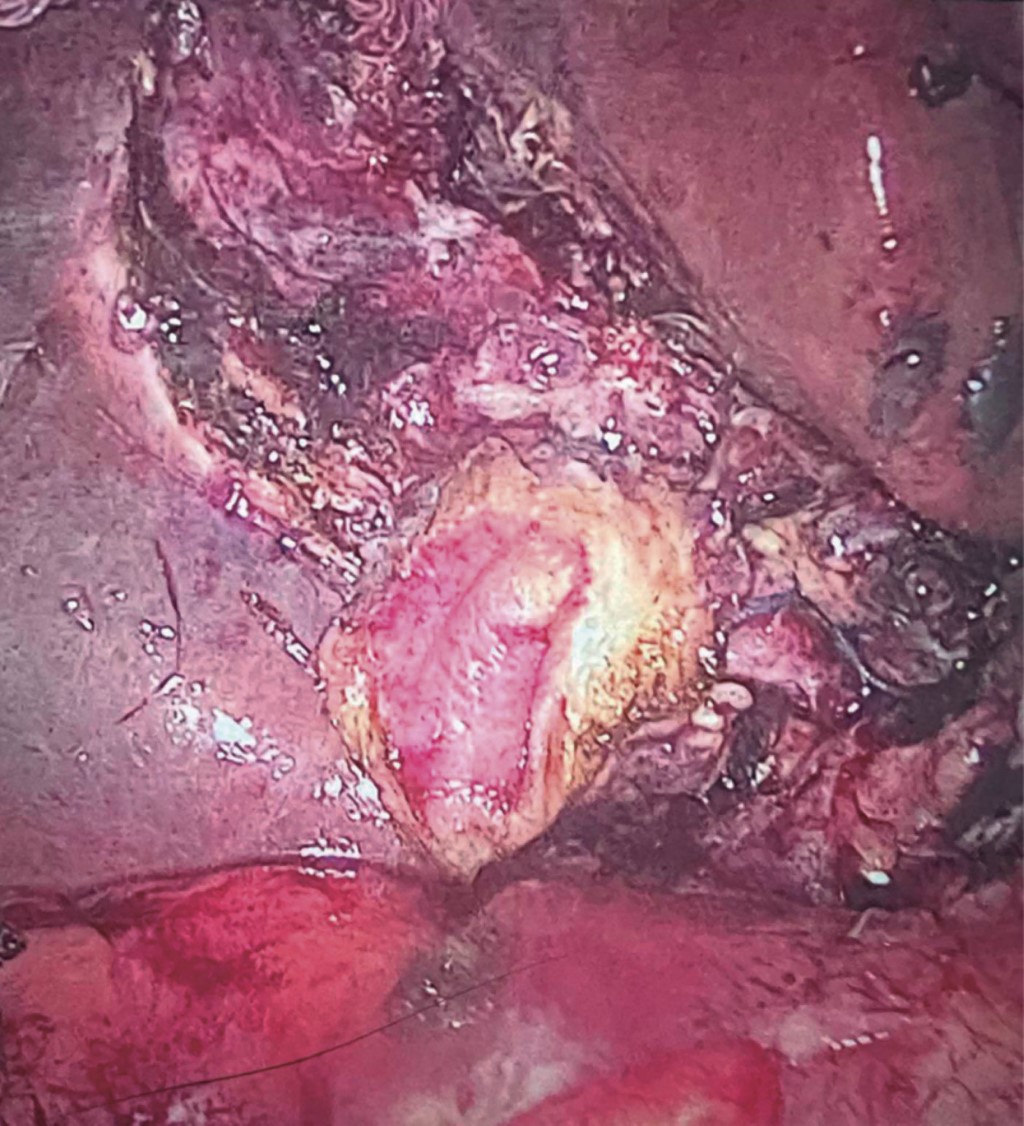

Subtotal cholecystectomy with Luper technique: an alternative management for a difficult cholecystectomy

Introduction: laparoscopic cholecystectomy is a very common and routine procedure, with more than 300,000 cholecystectomies performed in Mexico each year. Of these cholecystectomies, there is a large number of which are considered difficult cholecystectomies. These difficulties may arise due to the altered anatomy of the gallbladder, nearby organs or patient comorbidities, which increases the risk of complications and prolongs surgical time. Objective: to describe a subtotal cholecystectomy technique in which an endoloop is used to ligate the gallbladder remnant. Material and methods: a subtotal cholecystectomy technique was created in which a retrograde dissection of the gallbladder is performed to subsequently ligate the remnant using an endoloop. A retrospective study was carried out in which patients who were treated using this technique were evaluated. Results: nine subtotal cholecystectomies were performed with this technique at the time of writing this publication, in which the patients evolved favorably, all of them were monitored using a Penrose drain. There were no complications recorded in the postoperative period. Conclusions: it is important to note that, although the initial results of the technique are promising, they are based on a relatively small sample of patients. Therefore, an extension of the study with a larger sample is required to validate and generalize these results.

Figure 1

Figure 2

Figure 3

Figure 4